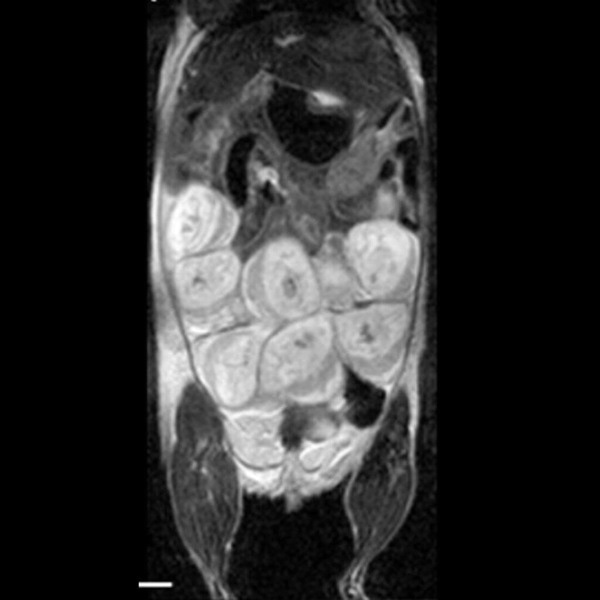

Hindlimb tumor growth: Monitoring the growth of xenograft tumor grown in the mouse hindlimb is identified with T2-weighted images. Segmentation of tumor region of interests (in red) on each tumor-containing slice allows accurate volume quantification. Image Credit: Scintica Instrumentation Inc

Monitoring the growth of xenograft tumor grown in the mouse hindlimb is identified with T2-weighted images. Segmentation of tumor region of interests (in red) on each tumor-containing slice allows accurate volume quantification. Image Credit: Scintica Instrumentation Inc